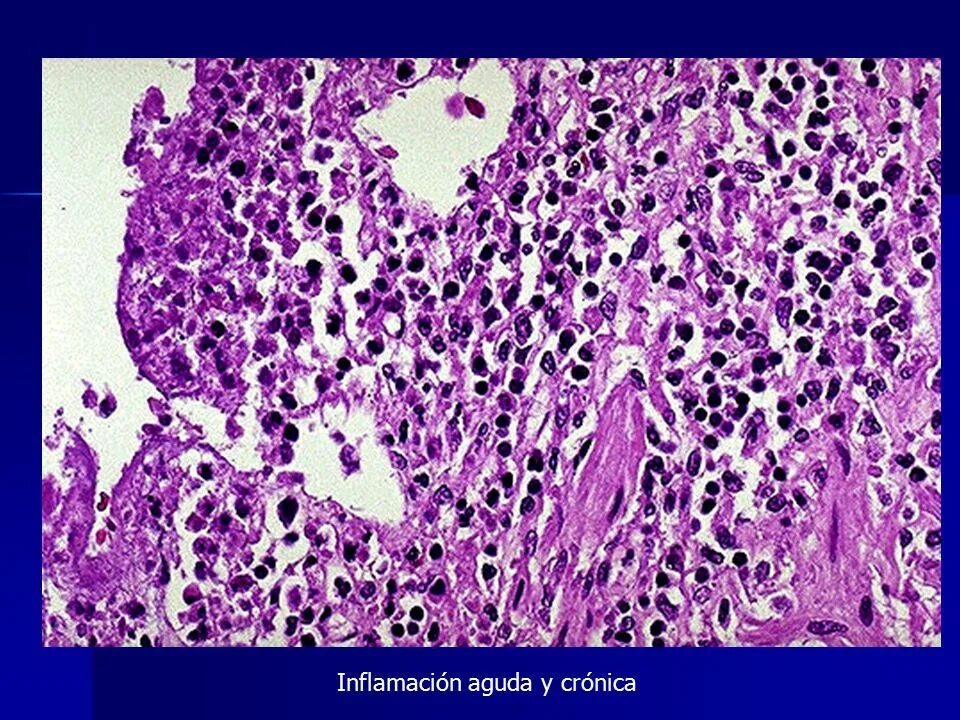

Диффузная лимфоцитарная инфильтрация